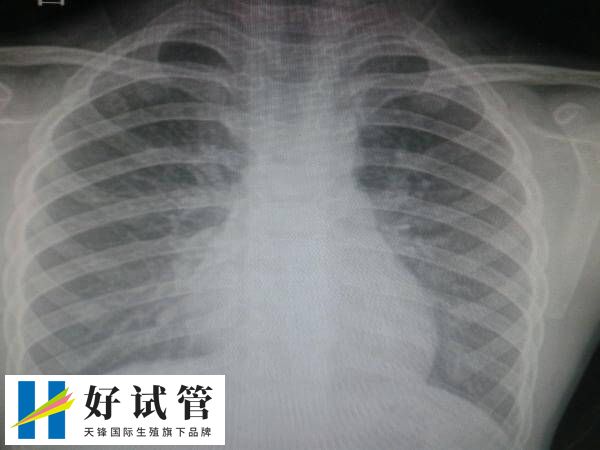

试管前做胸透为了检查什么_好试管网